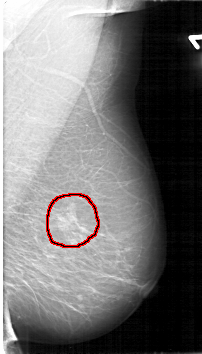

D_4125_1.RIGHT_MLO

FILE: D_4125_1.RIGHT_MLO.OVERLAY

TOTAL_ABNORMALITIES 1

ABNORMALITY 1

LESION_TYPE MASS SHAPE OVAL MARGINS ILL_DEFINED

ASSESSMENT 3

SUBTLETY 4

PATHOLOGY MALIGNANT

TOTAL_OUTLINES 1

BOUNDARY